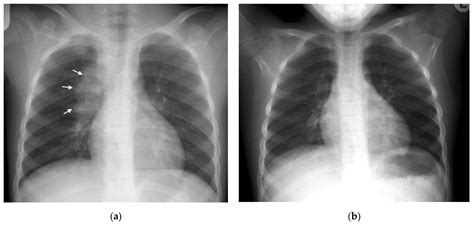

Interpreting Tb X Ray results requires expertise and experience. Radiologists look for specific signs that may indicate TB:

• Cavities: These are hollow spaces in the lungs that can form as the body tries to contain the infection.

• Nodules: Small, round opacities that can be indicative of TB infection.

• Infiltrates: Areas of increased density in the lung tissue, often seen in active TB.

It’s important to note that while Tb X Ray can provide valuable information, it is not always conclusive. Additional tests, such as sputum tests or CT scans, may be required for a definitive diagnosis.

• tb x ray vs normal